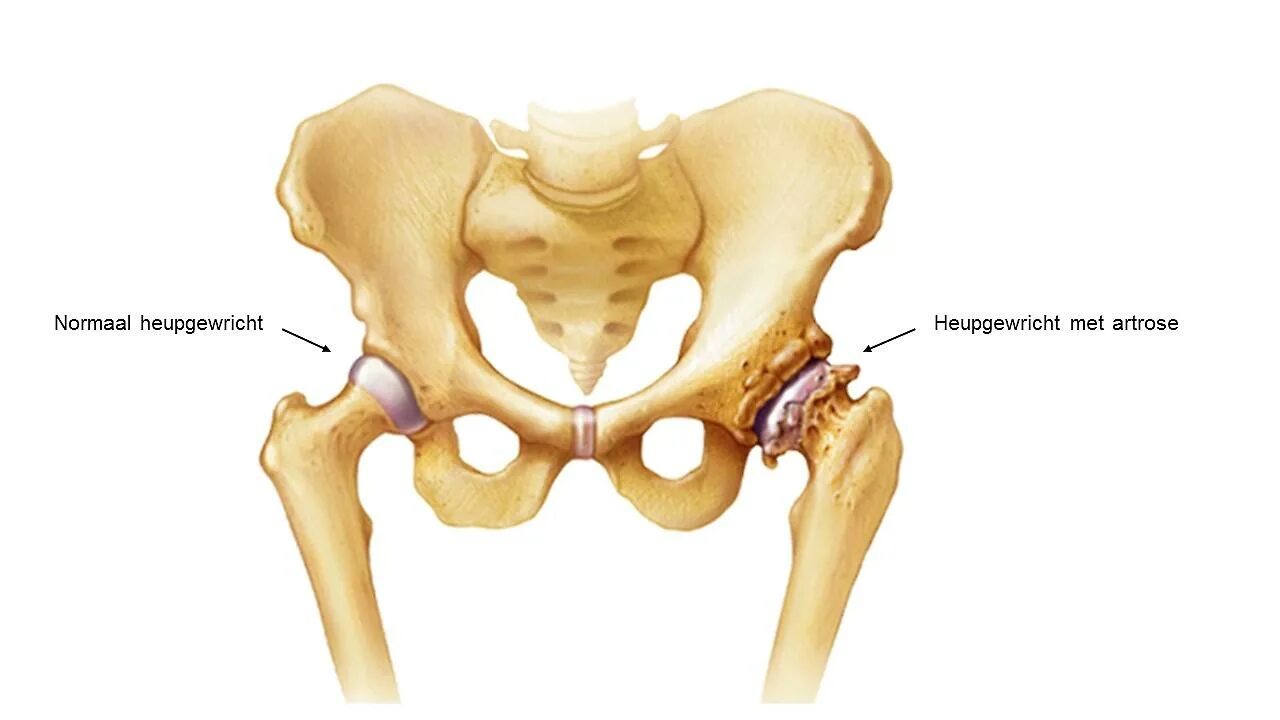

Артроз тазобедренного сустава симптомы у мужчин